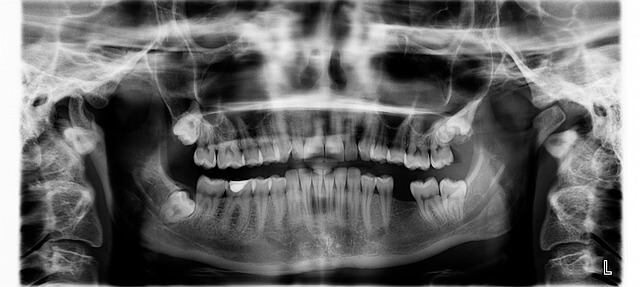

처음에는 단순히 양치할 때 피가 나는 정도로 생각했지만, 잇몸 염증은 생각보다 빠르게 번집니다. 제가 경험했을 때도 하루 이틀만 방심하니 잇몸이 붓고 씹을 때 통증이 심해졌습니다. 잇몸 염증의 주된 원인은 세균이 치석이나 음식물 찌꺼기 속에서 증식하면서 발생하는 것이었어요. 특히 피곤하거나 스트레스를 많이 받을 때 더 자주 올라왔습니다.

입속 환경은 외부보다 훨씬 습하기 때문에 세균이 활동하기 좋은 조건을 가지고 있습니다. 이 때문에 잇몸 염증은 단 한 번 생겨도 잘 재발하는 특징을 가집니다. 따라서 초기부터 꾸준히 관리하지 않으면 같은 부위에서 반복적으로 문제가 생길 수 있습니다.